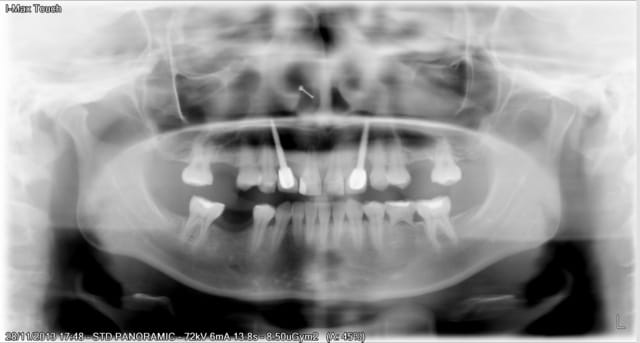

comment veux-tu que j'identifie ces implants avec une pano aussi pourrie sur laquelle je ne devine comme informations :

que les implants sont longs, et (en zoomant au maximum) qu'il y a des spires...

une rétro stp!!!! voir même 2, une pour la connexion et une pour la zone apicale

Ta pano, n'est pas géniale, donc de loin, je dirais que ça peut ressembler à du Tatum D1, mais il faut une radio meilleure, car ils me semble un peu fin pour du D1

un Tatum j'y crois pas...

je pencherais plus volontiers sur un implant "one piece" (monobloc) type Nobel direct ou similaire...

impossible à préciser avec une si mauvaise qualité d'image...

Voila la retro.

Cela doit etre le forum qui a reduit la resolution de ma pano qui a l´origine est bien meilleure.

Sauft pour l´apex des implants qui sont tellement longs et mal places quíls son en dehors du plan de coupe de la pano.